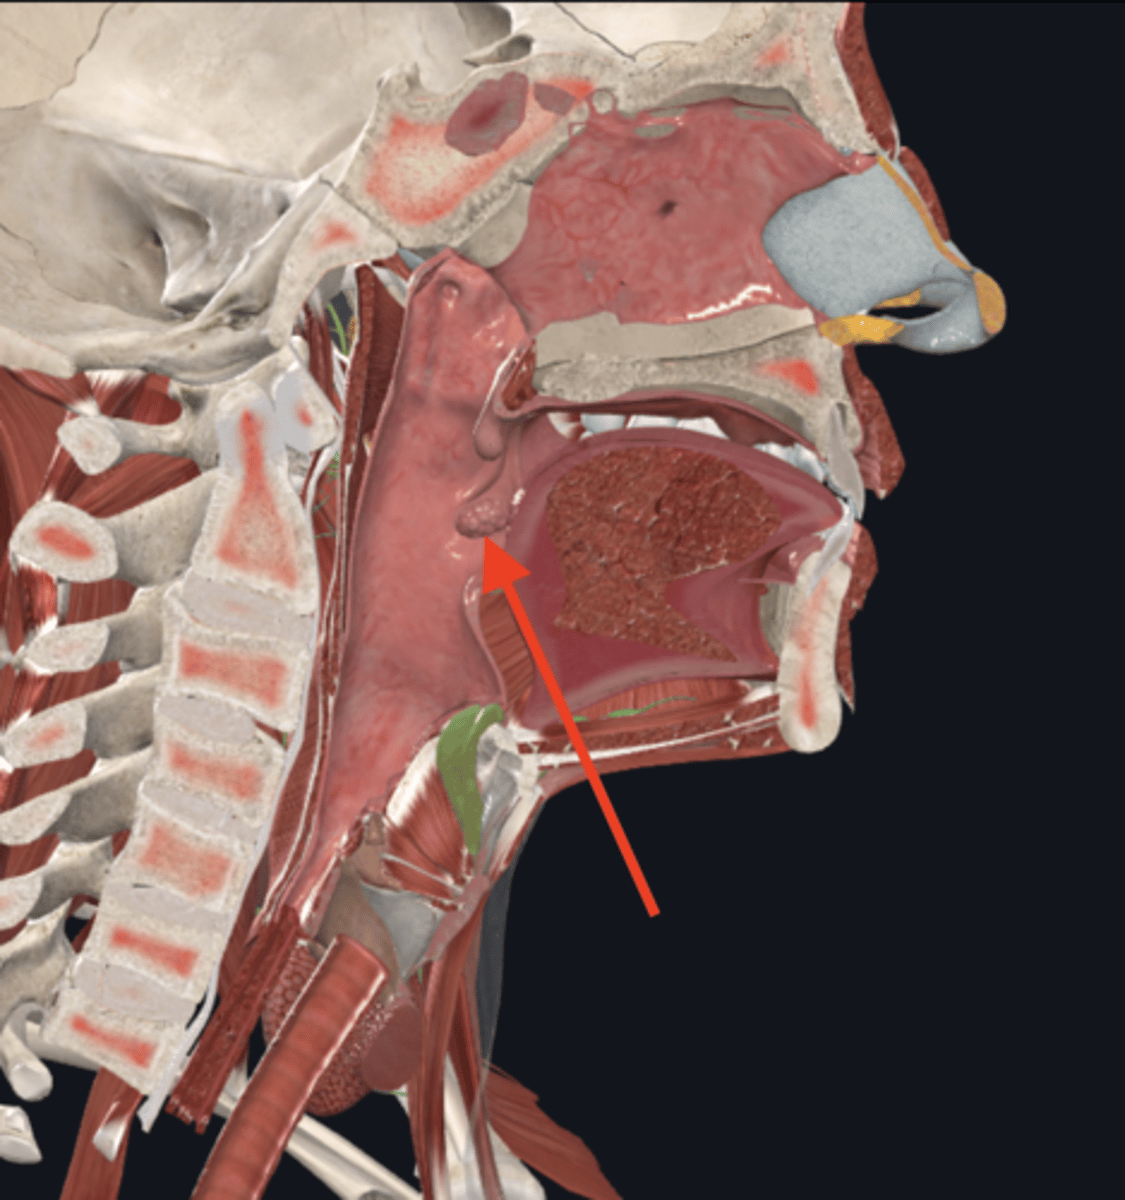

nasopharynx

name the circled region

oropharynx

name the circled region